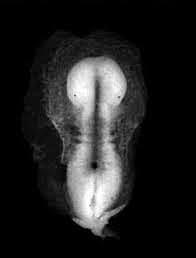

• Day 20- Secretory Phase (Stage 9)

Day 20- Secretory Phase (Stage 9)

Stage nine occurs during week three between 19 to 21 days. At this point, the embryo is about 1.5 to 2.5 mm in size.